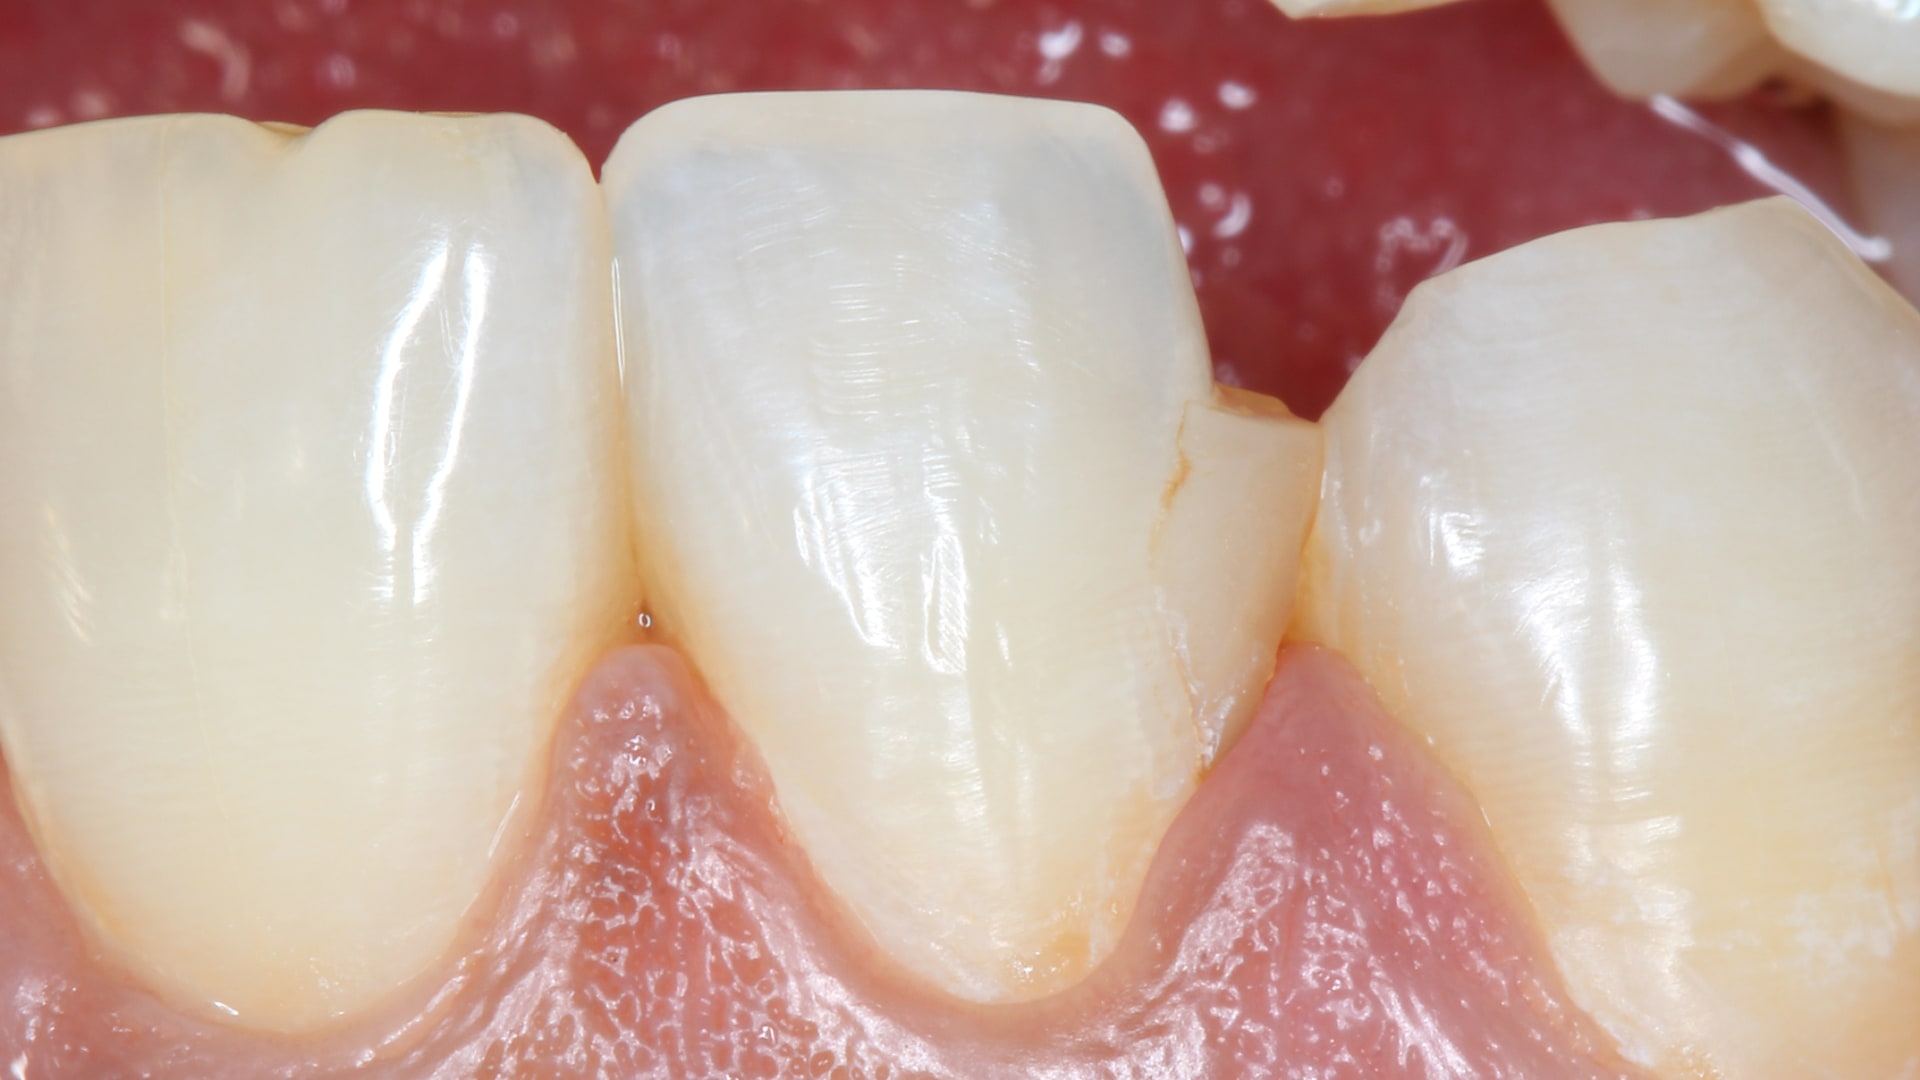

Simple Class III Picture

By Dr.Ali AlaaAdded on December 2025

Simple Class III

Easy peasy

Patient presented with caries in the medial aspect in the labial surface of the upper right lateral incisor. No symptoms related to the lesion. Spotte...

Read More